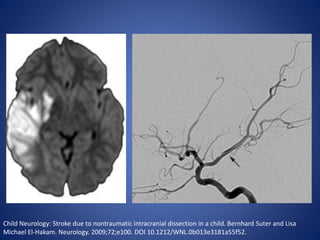

Trauma

• Dissection of the extracranial and intracranial portions of the

carotid and vertebrobasilar arteries is an important risk factor

for stroke in children.

• Occlusion or narrowness of the vesselʼs lumen by the

hematoma created within the arterial wall lead to cerebral

infarction distal to the lesion.

• Narrowing of the arterial lumen for up to several centimeters

“string sign” is diagnostic. However, tapering of the lumen to

complete occlusion is more common.

Child Neurology: Stroke due to nontraumatic intracranial dissection in a child. Bernhard Suter and Lisa

Michael El-Hakam. Neurology. 2009;72;e100. DOI 10.1212/WNL.0b013e3181a55f52.

Trauma • Dissection ofthe extracranial and intracranial portions of the carotid and vertebrobasilar arteries is an important risk factor for stroke in children. • Occlusion or narrowness of the vesselʼs lumen by the hematoma created within the arterial wall lead to cerebral infarction distal to the lesion. • Narrowing of the arterial lumen for up to several centimeters “string sign” is diagnostic. However, tapering of the lumen to complete occlusion is more common.

• 21.

Child Neurology: Strokedue to nontraumatic intracranial dissection in a child. Bernhard Suter and Lisa Michael El-Hakam. Neurology. 2009;72;e100. DOI 10.1212/WNL.0b013e3181a55f52.